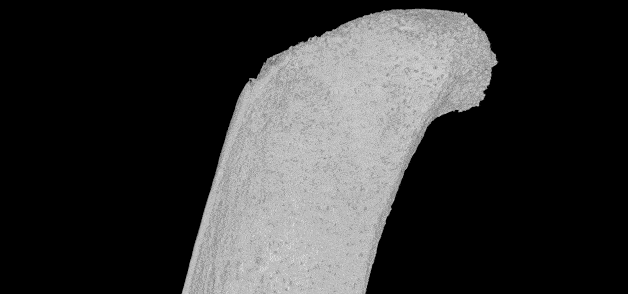

Схема строения транскортикального сосуда, проходящего через компактное вещество длинной кости. © Nature

Исследование опубликовано в журнале Nature. По словам его авторов, сеть мелких сосудов похожа на крошечные тоннели и проходит от поверхности костей в их внутренние полости. По всей видимости, благодаря им кровь и иммунные клетки, вырабатываемые в костном мозге, могут быстро и эффективно распространяться по всему телу.

Затем специалисты применили комбинацию нескольких методик, в том числе световой флуоресцентной микроскопии и рентгеновской микроскопии. Они заметили внутри костей, составляющих голень мыши, несколько сотен крошечных кровеносных сосудов, проходящих через твердый внешний слой.

Обнаруженные сосуды были названы транскортикальными.

Оказалось, что мышиная большеберцовая кость, которая по размерам меньше спички, может содержать более тысячи таких маленьких сосудов. Что удивительно, через их сеть проходит более 80 процентов артериальной крови и около 59 процентов венозной крови.

На следующем этапе команда решила проверить наличие подобных сосудов в костях человека. В результате оказалось, что кости людей также пронизаны сетью из сосудов нового типа, но более широкими по сравнению с мышиными.